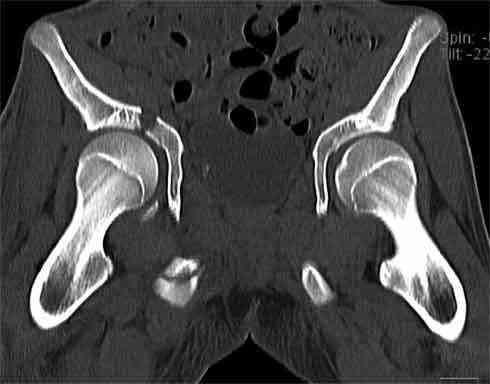

Не смог разглядеть на представленных картинках частичное повреждение левого КП, повреждение Денис1-2 справа? 3Д реконструкции в инлет и боковой проекциях убедительно не демонстрируют типа повреждения задних отделов тазового кольца(справа боковая масса скомпремирована), Наверное, у тебя есть возможность оценить тип перелома крестца по прямой проекции 3Д.

Думаю, что КТ заднего отдела показала бы ясно тип повреждения .

В данном случае 3D и корональные срезы КТ менее информативны, чем поперечные. Согласен с левосторенним минимальным повреждением КПС, но не смог уловить перелом крестца.

На 3D по линии перелома ацетабулум возможно сверху в подздошной кости уже есть сращение? или состояние перелома у молодых, после неполного (при пластической деформации) перелома.

По представленным материалам, мне кажется, перелом был передней колонны ацетабулум с минимальным вовлечением нагрузочной поверхности сустава, левосторенний повреждение КПС и лонных костей.